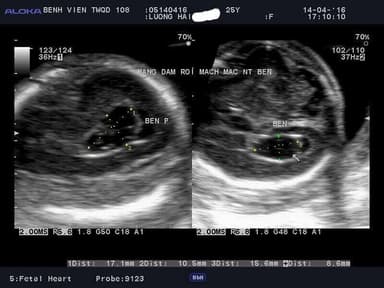

Thực hiện siêu âm để kiểm tra tình trạng ám rối mạch mạc 7mm